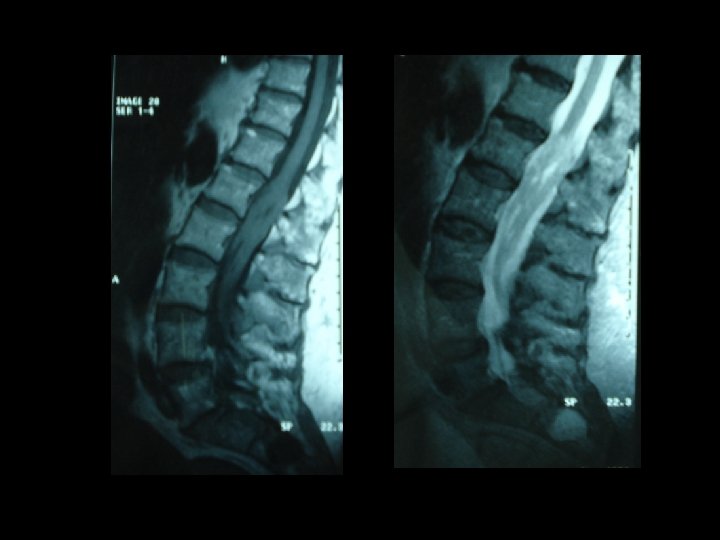

* Les examens biologiques misent en évidence une thrombopénie , une hypo albuminémie et une hypergammaglobulinémie modérée. Sérologie VIH était négative. * L’IRM lombaire pratiquée en séquence T 1, T 2 et avec injection du gadolinium montre un important épaississement des racines de la queue de cheval visible sur les coupes en séquence. T 2 qui se rehaussent intensément après injection du gadolinium.

* La présentation clinique n’est pas spécifique. * IRM médullaire : processus expansif étagé comprimant la moelle par endroit. * les lésions sont e hypo signal T 1, hyper signal T 2 et se rehaussant après injection du gadolinium. * l’IRM joue un rôle primordial dans le diagnostic des lymphomes à localisation médullaire.

* L'IRM vertébro-médullaire permet d'apprécier l'étendue de la tumeur et son extension vers les tissus mous et l'os permettant une orientation diagnostique et histologique. * Le diagnostic est histologique. * L'association radiothérapie chimiothérapie a prouvé son effet sur l'amélioration de la survie globale des patients.